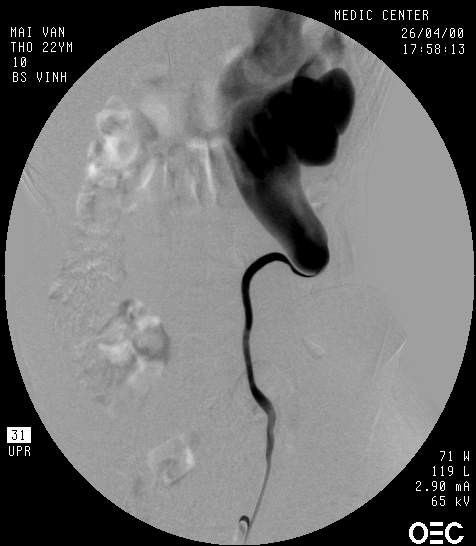

+ Nội soi bàng quang và chụp bể thận ngược dòng

• Xác định chiều dài của niệu quản bị ảnh hưởng

• Đặt stent JJ để giải áp tạm thời sự tắc nghẽn

Vài hình ảnh hẹp Khúc nối bể thận - niệu quản